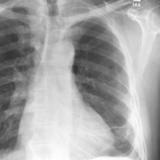

Rounded atelectasis case 1